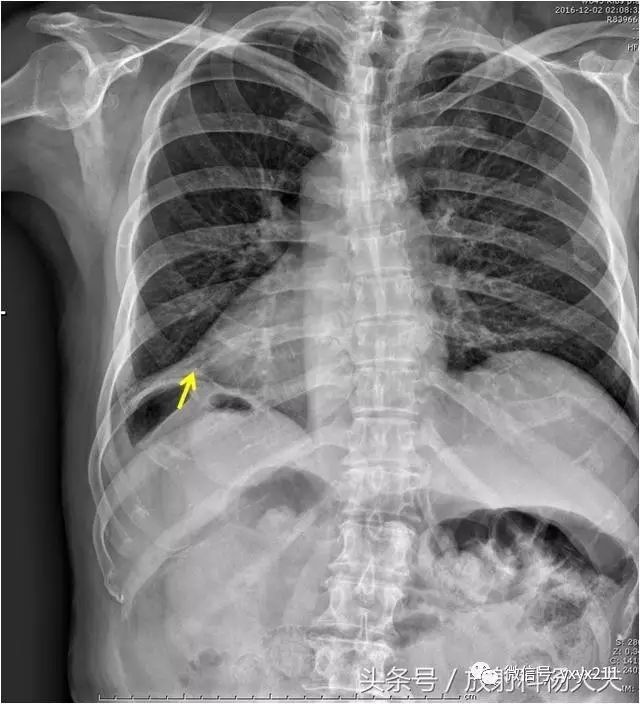

第 9 肋骨 骨折-肋骨の全体的な骨折では前述した通り第4肋骨~第8肋骨の骨折が多くなります。 しかし、ゴルフや野球のスイングなどによる疲労骨折のケースでは第4肋骨~第8肋骨だけでなく 第1肋骨 第2肋骨 の2箇所も疲労骨折を生じやすくなります。 一、第九根肋骨骨折是否严重 肋骨骨折容易并发以下的疾病,还是比较严重的: 1急性心力衰竭 肋骨骨折并发急性心力衰竭的病例多为多发性肋骨骨折,此病的患者早期应密切观察生命体征及病情变化,防止心肺功能衰竭,一旦出现早期症状应立即组织抢救,严防发生心跳骤停,心跳一旦停止不

症状: 休克 胸痛 无力 水肿 表现: 1、症状 偶尔由于剧烈的咳嗽 或喷嚏等,胸部肌肉突然强力收缩而引起肋骨骨折,称为自发性肋骨骨折,多发生在腋窝部的第6~9肋,当肋骨本身有病变时,如原发性肿瘤或转移瘤等,在很轻的外力或没有外力作用下亦可发生肋骨骨折,称为病理性肋骨骨折。我想问一下肋骨折了一根然后 如果肋骨折了插到肺里去会有生命危险吗? 本人今年51岁,四个月前上肋骨折接好后, 肋骨折后如何睡觉 ;